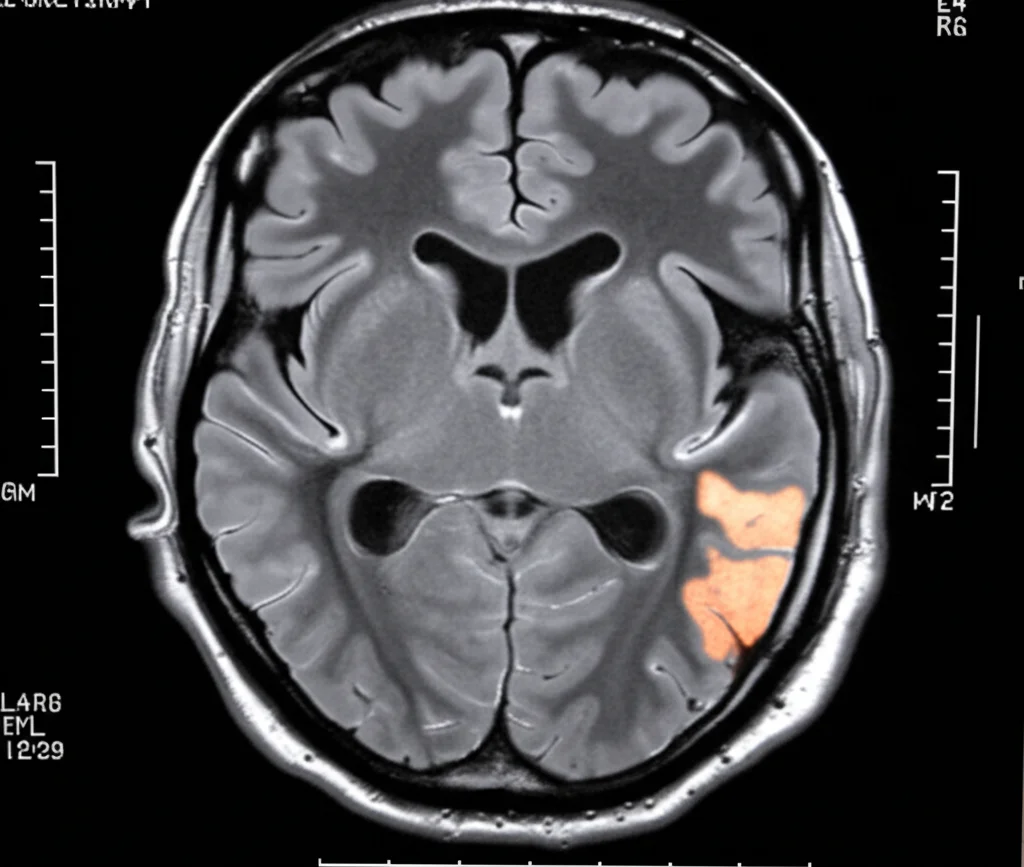

La segmentazione dei tumori cerebrali, cioè l’identificazione precisa dei loro confini nelle immagini mediche, è una bella gatta da pelare. Immaginatevi di dover disegnare il contorno esatto di una nuvola in continuo cambiamento: i tumori sono così, complessi, diversi l’uno dall’altro per forma, dimensione, posizione, e spesso si confondono con il tessuto sano circostante. Questo rende difficile per i medici pianificare terapie efficaci e riabilitazione.

Per visualizzare questi “intrusi” nel cervello, la risonanza magnetica (MRI) è lo strumento d’elezione, specialmente una sequenza chiamata FLAIR (Fluid-Attenuated Inversion Recovery). Questa tecnica è fantastica perché “spegne” il segnale del liquido cerebrospinale, facendo risaltare meglio l’edema (il gonfiore) attorno al tumore. Tuttavia, anche con la FLAIR, distinguere precisamente il tumore, specialmente le parti non attive, dal tessuto sano rimane complicato.

I numeri sono importanti, ma a volte un’immagine vale più di mille parole. Abbiamo confrontato visivamente le segmentazioni prodotte dal nostro modello con quelle di altri metodi e con le “verità” annotate dagli esperti. I risultati qualitativi confermano che DSIT-UNet riesce a localizzare i tumori con grande accuratezza e a tracciarne i bordi in modo molto preciso, anche in casi difficili.